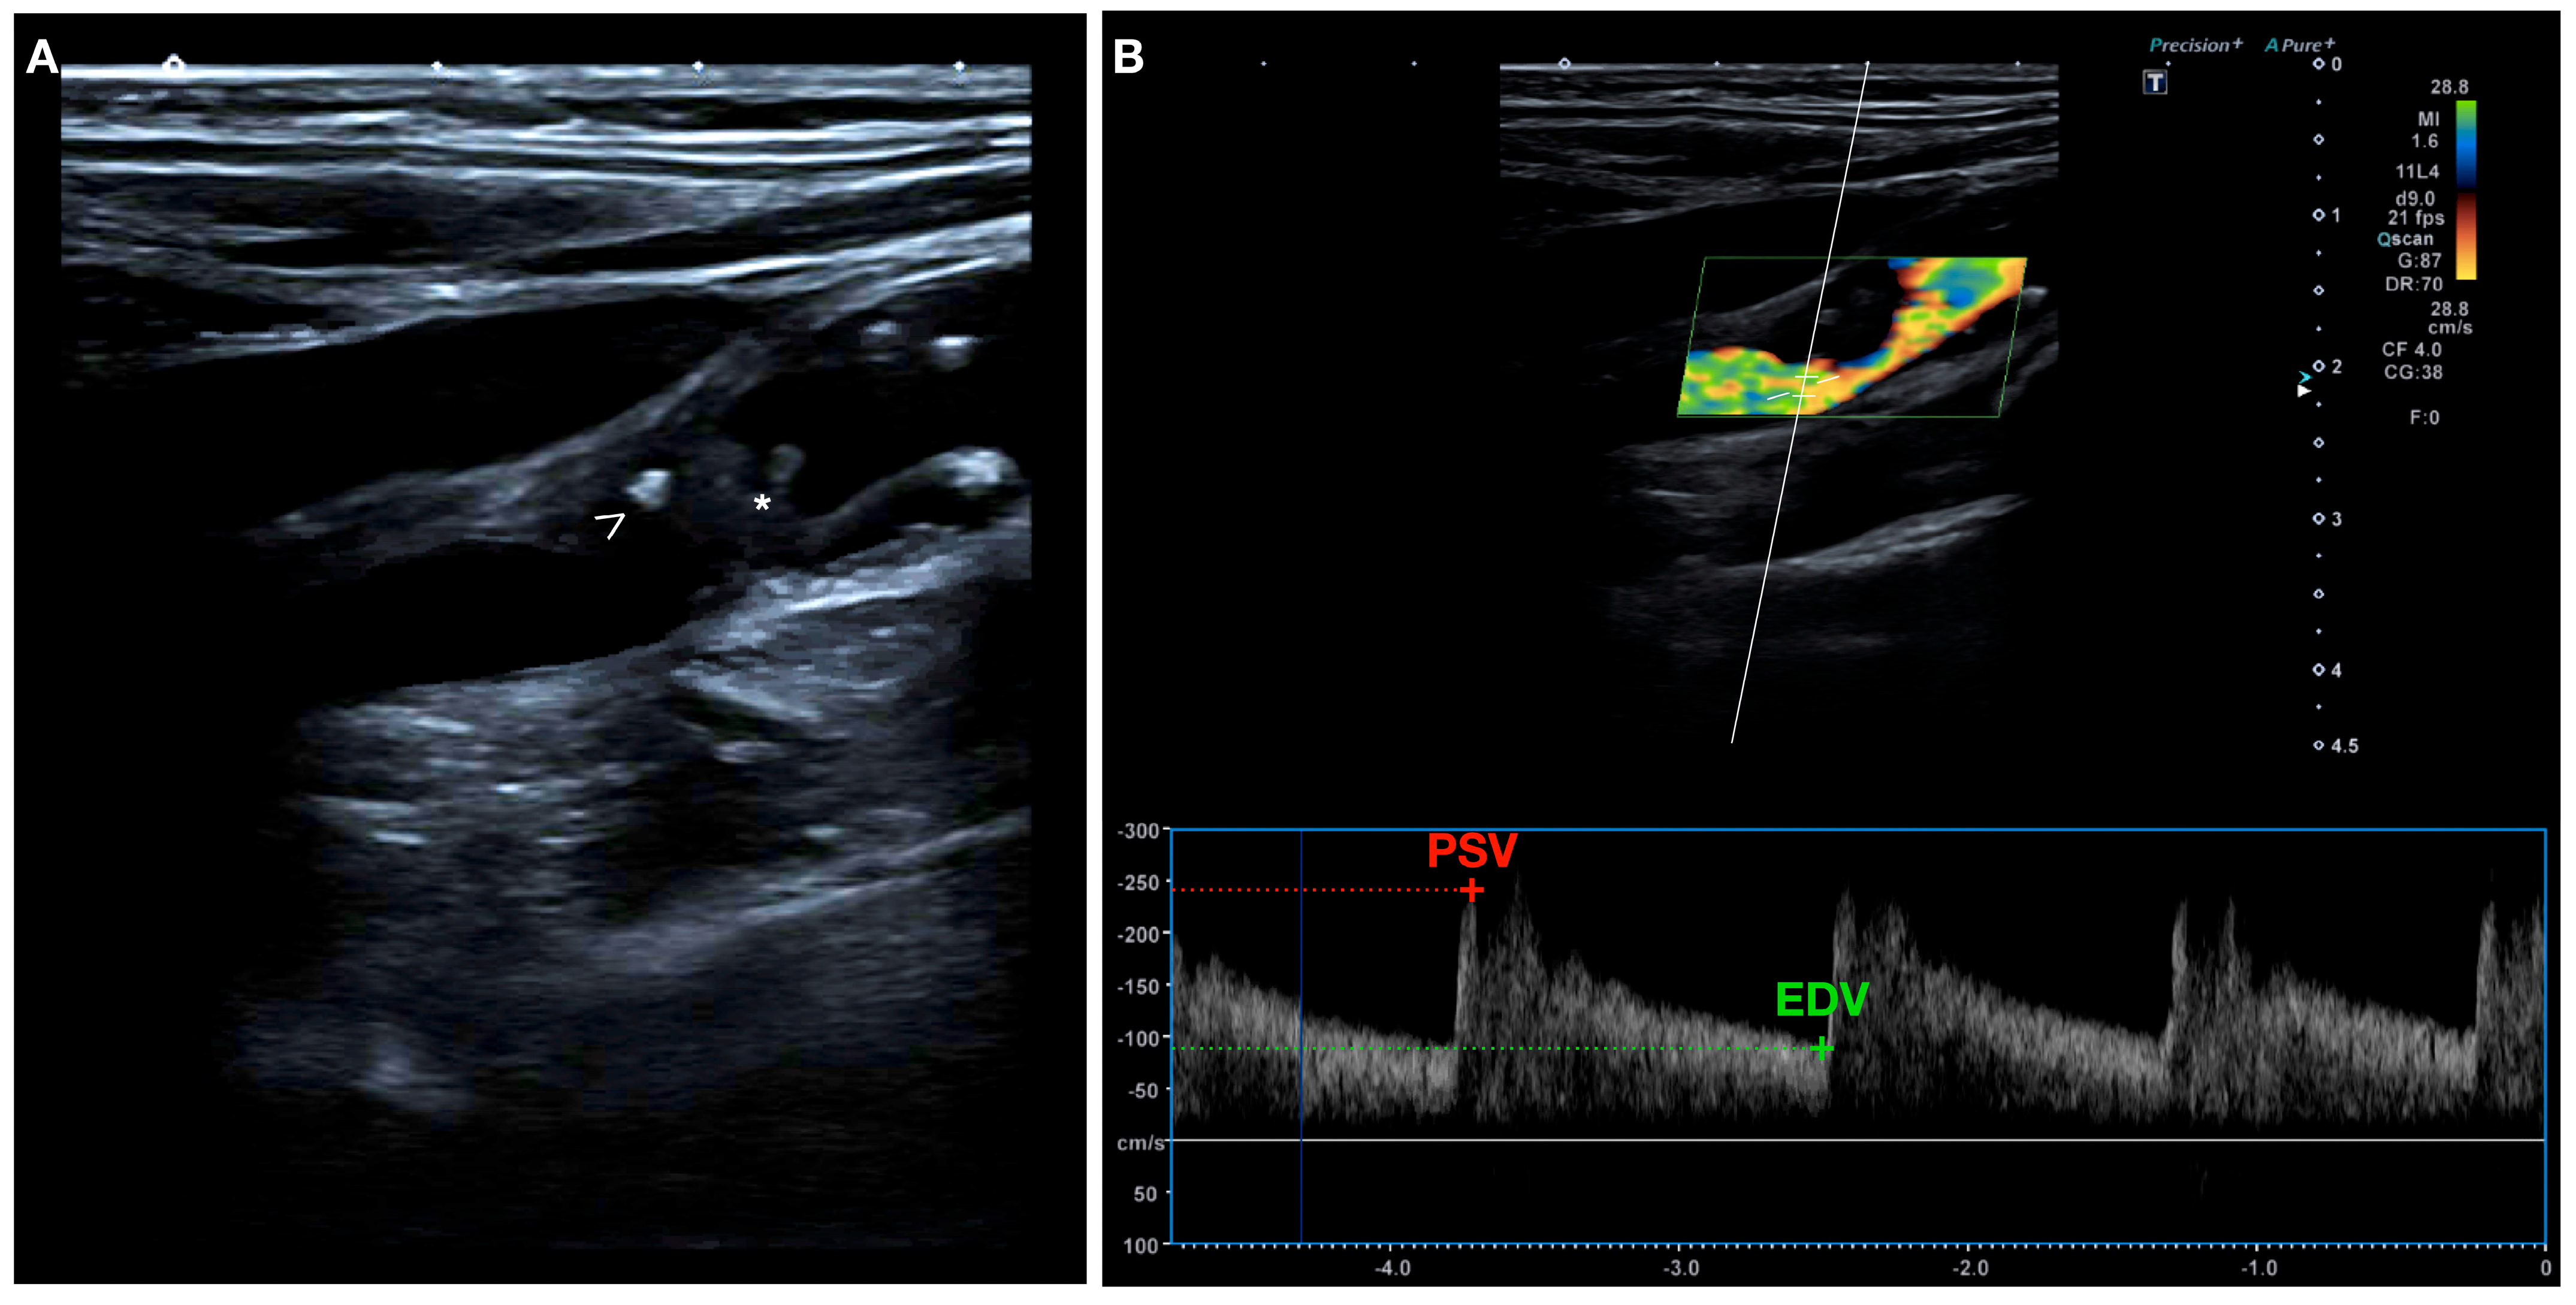

US has been widely used since the 1980s, particularly duplex ultrasonography, for quantifying the degree of carotid stenosis by measuring flow velocity and flow ratios, and it is the modality of choice for the initial evaluation of carotid artery disease [70,71]. In addition, it can also provide information on plaque instability based on the plaque surface and composition [72,73] (Figure 3).

Figure 3.

(A) B-mode ultrasound showing a longitudinal view of the internal carotid artery (ICA) with a heterogeneous echolucent plaque of irregular surface (*) and areas of focal calcification (arrow head). (B) High turbulence of the flow in the color Doppler study suggests the presence of severe stenosis. Spectral Doppler measurement of peak systolic velocity (PSV) = 245 cm/s, end diastolic velocity (EDV) = 90 cm/s, and ICA/carotid common artery (CCA) ratio = 3.7.